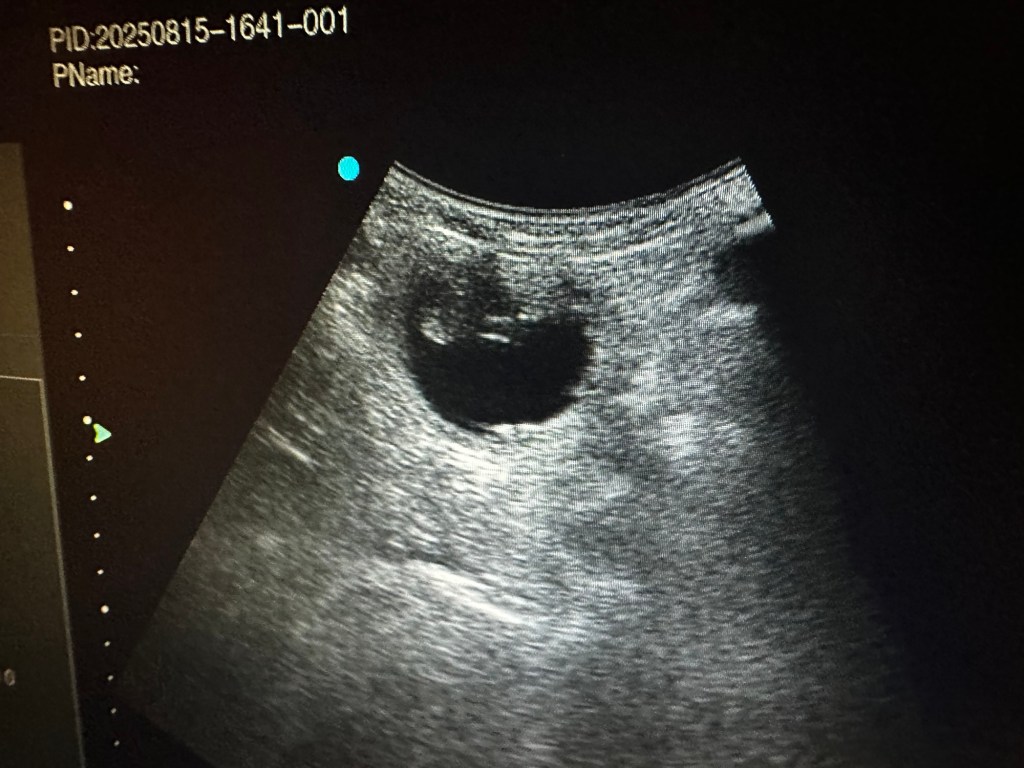

I dag har vi tatt ultralyd og begge tispene våre er drektige. Oliane med et lite kull og Naya med et stort kull. Elevene var med på ultralyd og nå er det bare å vente frem til røntgen uken før forventet termin.